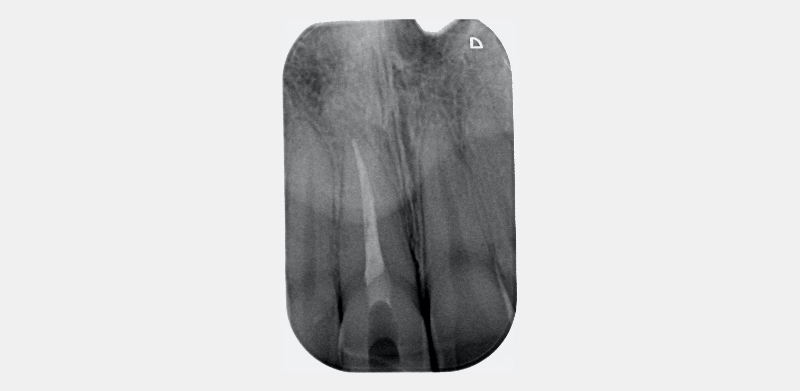

In this example of the Modified Walking Bleach Approach, the patient presented with a discolored upper right central incisor (1.1, Fig. 7). The old restoration was removed, an endodontic retreatment was carried out, and a coronal barrier seal was placed (Fig. 8). The access cavity was left open (Fig. 9).

The patient carried out the modified walking bleach technique with a nightguard for 48 hours (Fig. 10). I prefer to mark the night guard with a Sharpie marker to enable the patient to visualize the correct tooth to treat. The patient returned for review after successful whitening (Fig. 11).